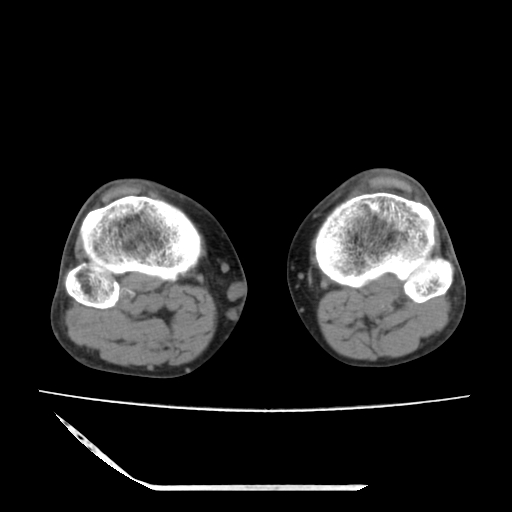

标题: CT13225:老年男性,左膝关节疼痛数月;请各位老师讨论。 [打印本页]

标题: CT13225:老年男性,左膝关节疼痛数月;请各位老师讨论。

骨质增生,骨性关节面硬化,关节积液,考虑退行性骨关节病

关节腔内少量积液,关节面退变。

双膝退变

骨质增生,骨性关节面硬化,关节间隙失常,关节积液,考虑退行性骨关节病.

骨质增生,骨性关节面硬化,关节积液,考虑退行性骨关节病。

这个病例诊断:退行性骨关节炎